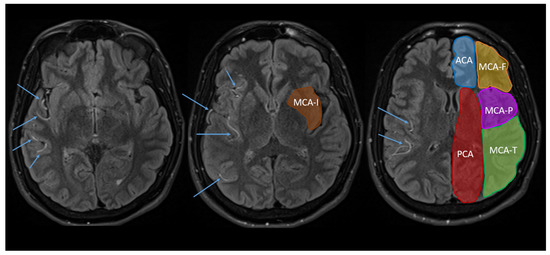

Reyes and colleagues proposed an alternative method for identifying hypoperfusion using fluid-attenuated inversion recovery (FLAIR) MRI sequences [10], which are routinely collected in stroke MRI protocols. Perfusion abnormalities on FLAIR present as a hyperintense signal in the arterial vessels, which appears as serpentine structures and/or isolated bright spots in the sulci (see Figure 1). FLAIR-hyperintense vessels (FHVs) are indicative of reduced blood flow [11,12], and thus may serve as an alternative avenue for the identification and quantification of hypoperfusion. Indeed, Reyes et al. developed the National Institutes of Health FHV (NIH-FHV) score to quantify the number and location of FHVs (in terms of the anterior cerebral artery (ACA), posterior cerebral artery (PCA), and four regions of the middle cerebral artery (MCA) territory). They demonstrated a strong significant association between the NIH-FHV scores and PWI lesion volume (i.e., one point on the NIH-FHV scale equated to about 12 mL of hypoperfusion on PWI). When controlling for lesion volume on diffusion-weighted imaging, the NIH-FVH was highly sensitive at detecting a mismatch ratio ≥ 1.8. However, Reyes and colleagues did not examine whether the location of FHVs corresponded to the location of the hypoperfusion in PWI.

Figure 1.

Examples of FHVs (indicated by the arrows) and vascular regions used for the NIH-FHV score: the anterior cerebral artery (ACA, blue), posterior cerebral artery (PCA, red), and four regions of the middle cerebral artery (MCA)—the MCA-frontal (MCA-F, orange), MCA-temporal (MCA-T, green), MCA-parietal (MCA-P, purple), and MCA-insular (MCA-I, brown). Note that no FLAIR imaging for the current study was shared by the NIH. Thus, this example of FHVs is from a participant in Bunker et al. [13].

2.3.1. FLAIR-Hyperintense Vessels

For the initial NIH-FHV scoring, FLAIR images were reviewed slice by slice and the presence of FHVs was scored from 0 to 2 in each of the six vascular regions in the lesioned hemisphere. A score of ‘0’ indicated no FHVs, a score of ‘1’ indicated 1–2 FHVs on 1–2 slices, and a score of ‘2’ indicated 3+ FHVs on one slice or 3+ slices with FHVs. Scores for each region were summed for a total score out of 12 for the hemisphere, with higher scores suggestive of a greater volumes of hypoperfusion. The six vascular regions (see Figure 1) were the ACA territory, the PCA territory, and four sub-regions of the MCA territory (frontal (i.e., MCA-F), temporal (i.e., MCA-T), parietal (i.e., MCA-P), and insular (i.e., MCA-I)). Since the purpose of this study was simply to identify the association between the location of hypoperfusion across FLAIR and PWI MR techniques, these scores were recoded as a binary variable, indicating that FHVs—or hypoperfusion—were/was present or absent in each region. Hence, a score of 1–2 in any of the six regions was recoded as 1, for ‘present’, or 0, for ‘absent.’ The relationship between total FHV scores (i.e., severity of hypoperfusion) and PWI volumes are reported elsewhere [10].